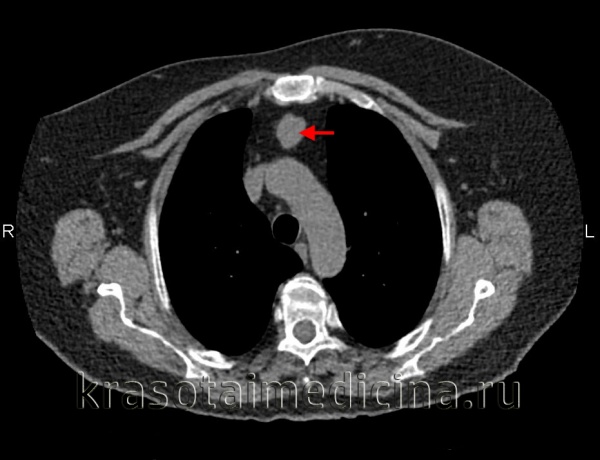

При полипозиционной рентгенографии грудной клетки в типичных случаях определяется шаровидная или овальная гомогенная тень средней интенсивности, с четкими контурами. При наложении тени средостения на тень кисты дополнительно требуется проведение пневмомедиастинографии или рентгенографии пищевода с бариевой взвесью. Установить анатомические взаимоотношения бронхогенной кисты с трахеобронхиальным деревом позволяет бронхоскопия и бронхография. При наличии признаков сдавления верхней полой вены или грудного лимфатического протока целесообразно выполнение флебографии и лимфографии.

Отличительным признаком тонкостенных бронхогенных кист служит изменение их конфигурации и положения при введении газа в средостение или плевральную полость (в отличие от дермоидных кист с толстой стенкой или плотных опухолей средостения). МСКТ грудной клетки в ряде случаев позволяет отказаться от проведения инвазивной диагностики бронхогенных кист и заранее спланировать объем вмешательства, поскольку дает исчерпывающую информацию о локализации и размерах образования.

- Рентгенологические исследования. Полипозиционная рентгеноскопия и рентгенография грудной клетки, рентгенография пищевода и сердца, пневмомедиастинография позволяют определить локализацию, форму и размеры кисты, ее связь с соседними органами, изменение положения при дыхательных движениях.

- Томографическая диагностика. Для более детальной оценки структуры, толщины стенок кисты, характера содержимого и взаимоотношения с соседними анатомическими образованиями, производится КТ и МРТ средостения.